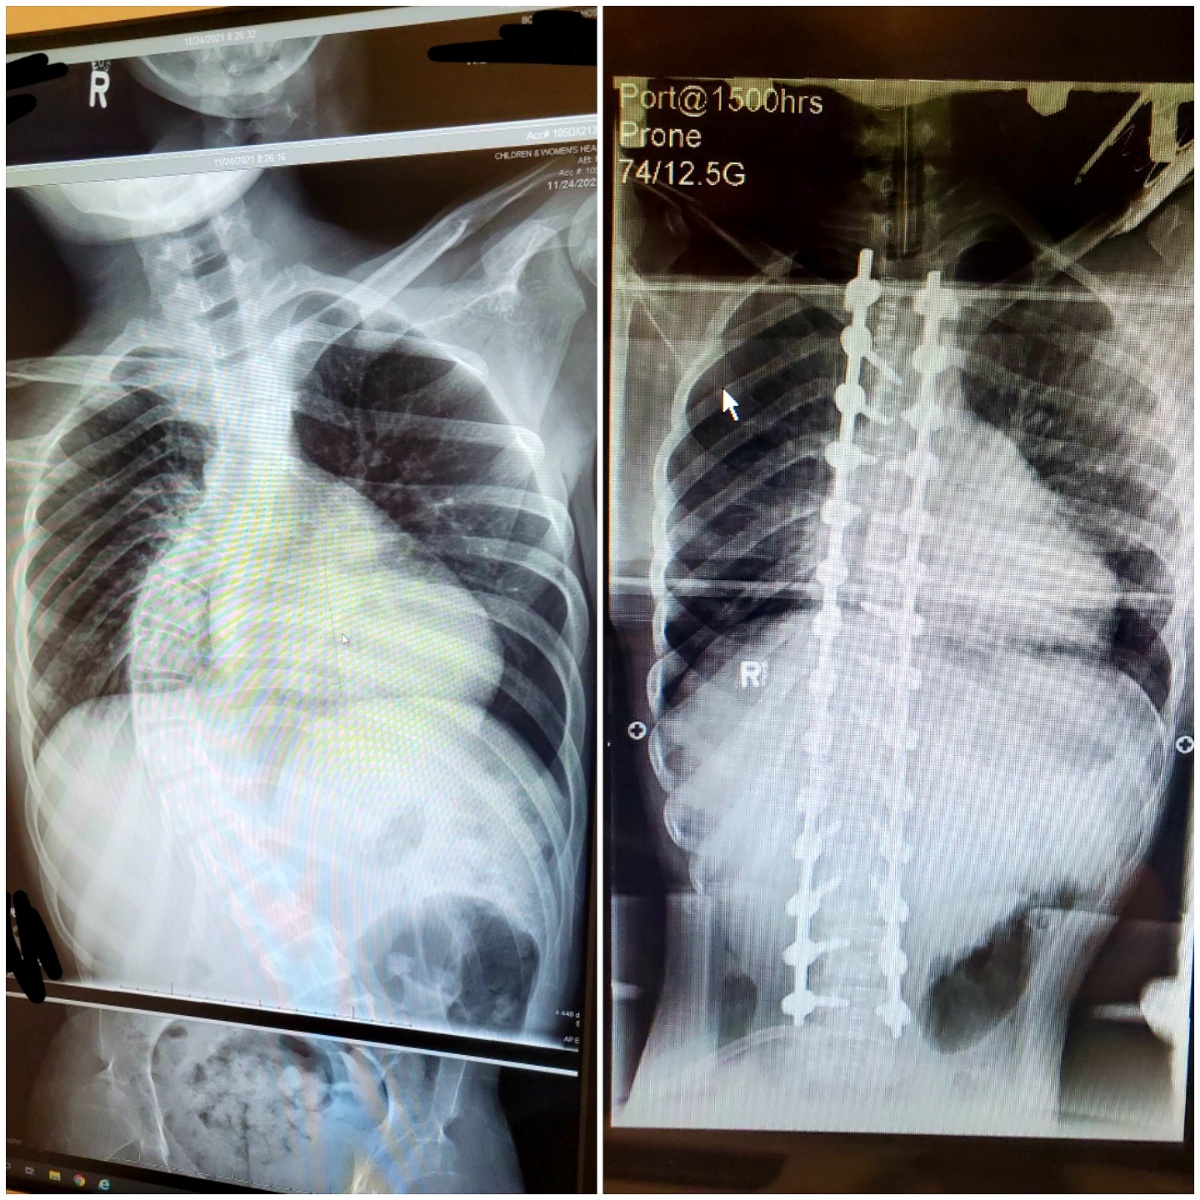

The Gallant family from Fort St. John has been trying to get their son Devin surgery to correct a worsening curve in his spine.

Devin has Type-3 Spinal Muscular Atrophy (SMA), a genetic disease that causes the body’s muscles to waste away.

But one day before Devin’s 15th birthday, he underwent surgery at B.C. Children’s Hospital and has already been discharged from the ICU.